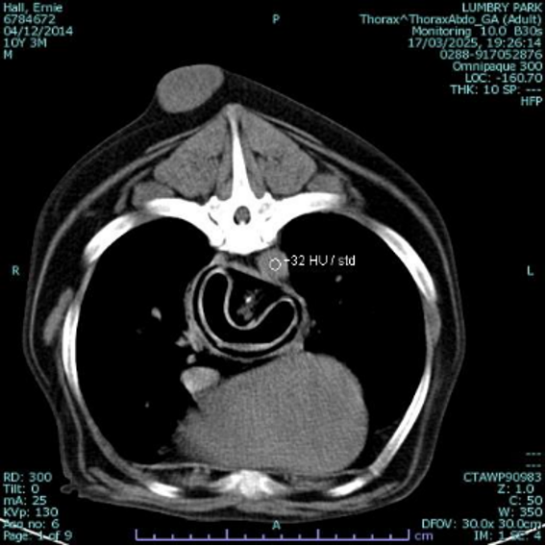

A gastric foreign body was suspected, but CT imaging revealed a different problem — a large, intact object lodged in the caudal oesophagus. Despite being compressed in shape, it was clearly consistent with a tennis ball and was completely obstructing the lumen. Given the risk of perforation and stricture formation, immediate intervention was required.

A CT scan revealed a foreign object lodged in Ernie's oesophagus.